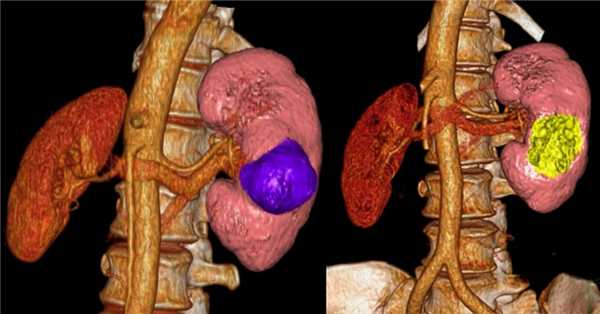

3D-реконструкции опухоли Вильмса пациентов детского отделения НМИЦ онкологии им. Н.Н. Петрова

Опухоль Вильмса. Компьютерная томография